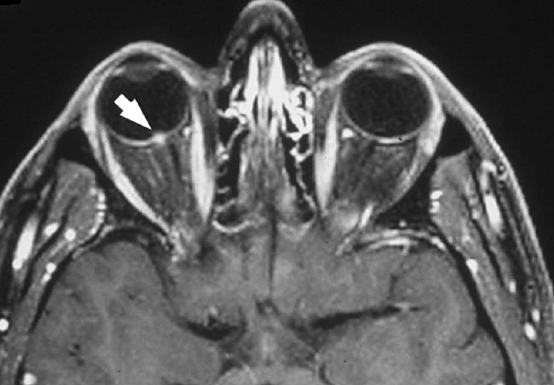

In general, neuroimaging studies in neuroretinitis are normal and not generally required for diagnosis. There are few reports of abnormal neuroimaging studies in patients with neuroretinitis in which the MRI demonstrated abnormalities of the optic nerve . The fat-suppressed contrasted enhanced axial T1 weighted orbital MRI below shows right intravitreal optic nerve enhancement (arrow) which would be expected with severe disc edema. Retrobulbar enhancement (like in optic neuritis) is rare, but reported.

Hence, there appears to be a spectrum of neuroimaging findings in neuroretinitis:

- Normal optic nerve

- Intraocular optic disc enhancement at the nerve-globe junction (below)

- Optic nerve sheath enhancement (optic perineuritis)

- Optic nerve and optic sheath enhancement